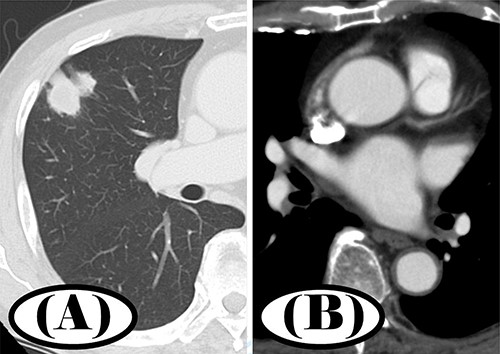

A 78-year-old man was diagnosed with a 3.0-cm nodule in the right upper lung field on chest X-ray during a routine visit for the treatment of chronic atrial fibrillation (AF) and hypertension. Chest computed tomography (CT) showed a 3.0-cm-diameter nodule with a substantial component of pleural depression in the S3 segment of the right upper lobe (Fig. 1A).

Preoperative chest CT; (A) a 3.0-cm nodule in S3 segment of the right upper lobe was found in pulmonary window setting; (B) contrast-enhanced CT showed no thrombus in the left atrium.

Fluorodeoxyglucose/positron emission tomography CT showed abnormal accumulation (maximum standardized uptake value [SUVmax] = 6.14) consistent with the lesion being located in the right upper lobe nodule. There were no other obvious abnormal findings. Contrast-enhanced CT revealed no obvious thrombus in the left atrium (Fig. 1B). Bronchoscopy was considered in the differential diagnosis. However, the patient had received warfarin for the treatment of chronic AF, and imaging findings were strongly suggestive of lung cancer.